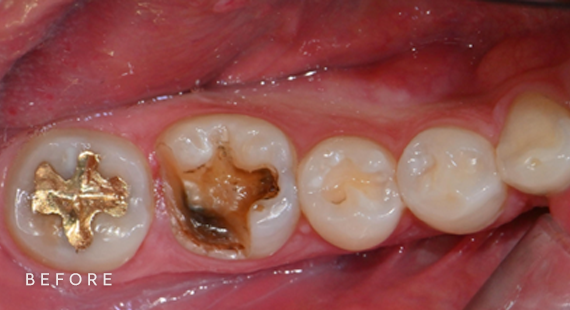

충치치료